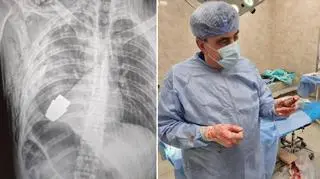

Operacja przebiegła pomyślnie, ranny żołnierz przechodzi teraz rehabilitację i rekonwalescencję. "Nie każda rana w pobliżu serca jest śmiertelna!" - podkreśliła wiceminister. Opublikowane przez nią fotografie pokazują spory pocisk widoczny na zdjęciu rentgenowskim klatki piersiowej rannego żołnierza i ten sam pocisk wydobyty już przez chirurga.